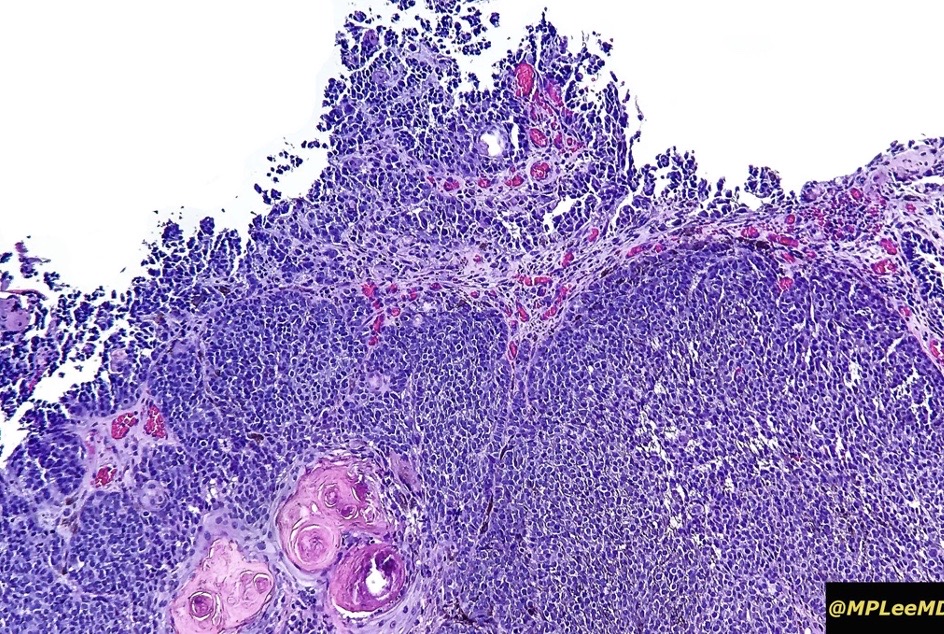

An exceedingly rare collision tumor composed of an admixture of squamous cell carcinoma/basal cell carcinoma/trichoblastoma respectively and melanoma. Although most appear to have behaved in a benign fashion, a malignant basomelanocytic tumor is illustrated below. More cases will be need to be stidies/published before the true biological behavior of this group of tumors can be satisfactorily elucidated. I think that complete excision should be the rule and a careful follow-up recomended.

Basomelanocytic tumor

Squamomelanocytic tumor